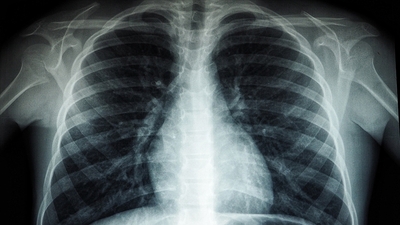

Hayatın hemen her alanında insanların maruz kaldığı plastiklerin vücut üzerindeki etkilerine her geçen gün bir yenisi ekleniyor. Son olarak İngiltere'de yapılan araştırma, yaşayan insanlardan alınan akciğer dokularında küçük plastik parçacıkları (mikroplastik) tespit edildiğini ortaya koydu.

Mikroplastiklerin günlük hayatın her yerinde görüldüğünü belirten Marmara Üniversitesi Pendik Eğitim ve Araştırma Hastanesi Göğüs Cerrahisi Anabilim Dalı'ndan, Prof. Dr. Bedrettin Yıldızeli, "Mikroplastik adı verilen polipropilenler günlük hayatımızda her yerde karşılaştığımız plastik maddelerdir.

Yemek yediğimiz plastik kaplardan tutun, kullandığımız arabada ve jelatinlerde de görebiliriz. Dolayısıyla günlük hayatımızda bu maddelere çok fazla maruz kalmaktayız. Hava kirliliğinin yoğun olduğu büyük şehirlerde de görülüyor. Zaten 20 yıl önce ortaya çıkan bazı çalışmalarda akciğer kanseri sebebiyle ameliyat olmuş hastaların akciğer dokularında bu mikroplastik adı verilen yabancı maddeleri görmüştük. Bu maddeler vücudumuza solunum yoluyla girdiğinde yaygın derecede reaksiyon yapmaktadır. Buna bağlı olarak akciğerde kansere kadar yol açabilen çeşitli hastalıklar görmekteyiz. Astım, akciğer hastalığı gibi hastaları tetiklediğini görüyoruz" şeklinde konuştu.

Yıldızeli, mikroplastiğin kansere de yol açtığını ifade ederek, "Özellikle meslek hastalıklarında bu durumu görüyoruz. Hastalarımızda, nefes darlığı, egzersiz kapasitelerinde düşme ve öksürük görülüyor. Bu çalışmayla birlikte meslek hastalığı olmayan bizim gibi normal insanlarda da plastik maddelerin akciğerimize geldiğini gördük. Normalde bir şeyi soluduğumuz vakit bunun akciğerlerimize kaçması ve aşağılara gitmesi mümkün. Ancak bizim daha aşağıda ufak dediğimiz damarsal düzeydeki yapılarımızda bile mikroplastikler görülebiliyor. Vücut bunu parçalayamadığı için bu kansere kadar yol açar. Mikroplastikler sigara içenler gibi riskli gruptakilerde kanser, astım gibi hastalıklara neden olur" diye konuştu.